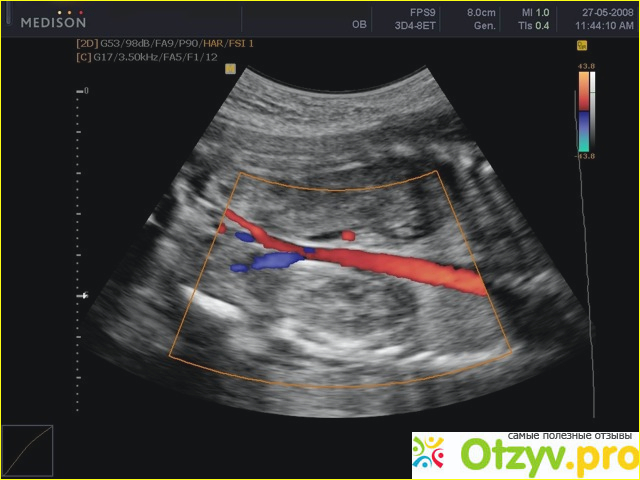

Что врач узист увидит на УЗИ . Он оценит состояние сосудов , как работают кровооттоки , какое состояние артерий Есть ли бляшки или же слишком разжижена кровь. Всё это видно на узи. А лучше если это доплер-узи. То есть можно высчитать всё до мелочи. На сколько сужены ил расширенны сосуды. Конечно же на основании протокола узи врач может оценить ваше состояние и назначить лечение. Срази пишу, что лучше самостоятельно не пытаться разобрать что написано в заключении. Это сделает врач ))

Узи брахиоцефальных сосудов головы и шеи | БЦА | ЦДС БЦА | УЗИ сосудов шеи (7 Съезд РАСУДМ УЗИ) |